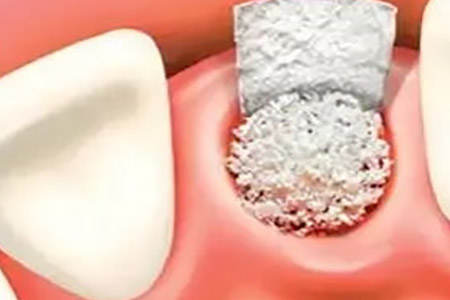

有些患者因为牙齿缺失的比较早,或牙龈发生了萎缩,那么就常常导致牙槽骨中的骨量不足,此时就得进行骨粉的植入,只有这样才能完成牙齿的种植,以免种植后牙齿不稳定,不仅浪费金钱对牙龈的创伤也不小。

牙齿种植中使用的骨粉主要有三种,人工骨粉、自身骨粉,以及自身和人工混合。

人工骨粉,是人工骨粉填补牙槽骨缺损的部位,然后再用人工生物膜覆盖,让你自然生长。人工骨粉不需要从自身取骨,而且骨吸收的速度会比较慢,目前使用的很多。

自身取骨,通常是在手术区域骨量丰富的地方取骨,再植入到骨缺失的区域,这种在一定程度上价格低廉,不过吸收很快,运用比较少。

自身和人工混合,这是在需要骨量比较多的时候运用的,在吸收度上居中。

牙齿种植前医生会对骨量进行检查,若情况不合符将会采用植粉的操作,至于植入的多少还需看患者的实际情况才能明确。骨量缺失的越多那么需要植入的也就越多,当然所需要的费用也就比较高。